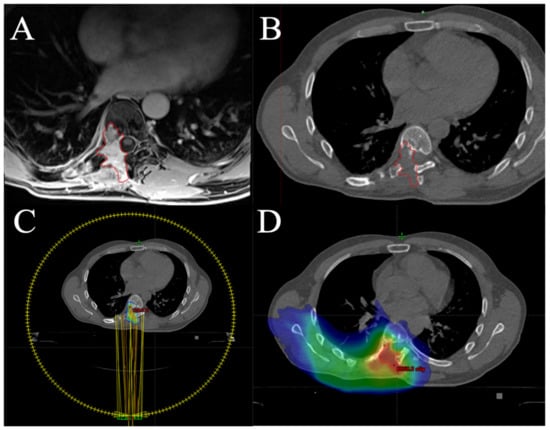

6. Radiotherapy in Chondrosarcoma

- Andrä, C.; Eze, C.; Ganswindt, U.; Roeder, F.; Belka, C.; Ostermann, H.; Manapov, F. Simultaneous bilateral stereotactic body radiation therapy of two inoperable centrally located pulmonary lesions in a patient with metastatic mesenchymal chondrosarcoma. Cancer Treat. Commun. 2016, 6, 8–10. [Google Scholar] [CrossRef]